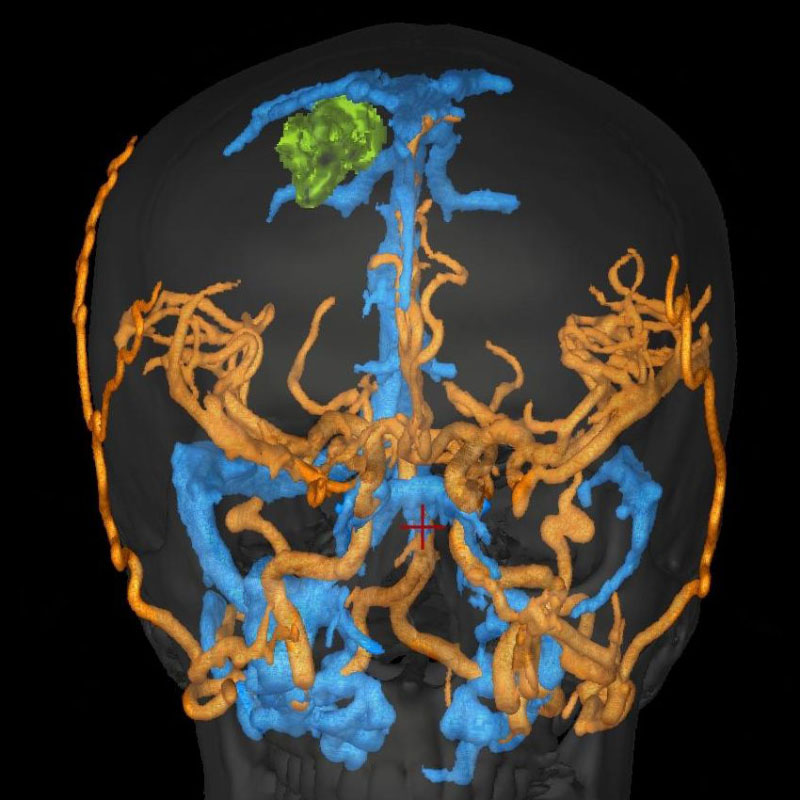

'25年1月

50代

南田,野本

右小脳

出血性海綿状血管腫

再出血の予防目的

兵庫県の病院

より紹介

No.No.59 手術前1

No.No.59 手術前2

No.No.59 手術後1

No.No.59 手術後2

CT/MRにより完全に摘出されたことが確認された